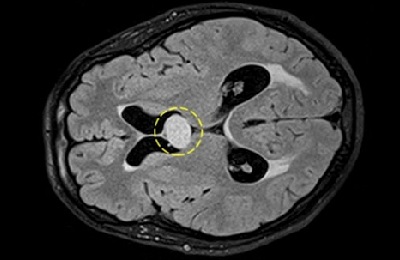

Такая аномалия представляет собой очаговое скопление жидкости в структурах формирующегося сосудистого сплетения головного мозга. Данную аномалию корректнее называть псевдокистой, ведь она не имеет собственной капсулы, следовательно, и собственного отграниченного содержимого.

Пока эти сплетения формируются, они еще не совершенны и не справляются полноценно с возложенной на них функцией. В зоне их формирования возможны очаговые скопления продуцируемой ими же спинномозговой жидкости. На УЗИ такие скопления будут иметь признаки кистозной полости, по причине чего их и называют кистами сосудистых сплетений.

Кисты, локализующиеся в сосудистом сплетении мозга, представляют собой относительно редкое явление, которое вызывает интерес у специалистов. Врачи отмечают, что основными причинами их развития могут быть как врожденные аномалии, так и приобретенные факторы, такие как инфекции или травмы. По мнению нейрохирургов, большинство таких кист не вызывает серьезных симптомов и часто обнаруживается случайно при проведении МРТ. Однако в некоторых случаях они могут приводить к повышению внутричерепного давления или другим неврологическим нарушениям. Прогноз при данной патологии, как правило, благоприятный, особенно если киста не увеличивается в размерах и не вызывает клинических проявлений. Важно, чтобы пациенты находились под наблюдением специалистов, чтобы своевременно выявить возможные изменения в состоянии.